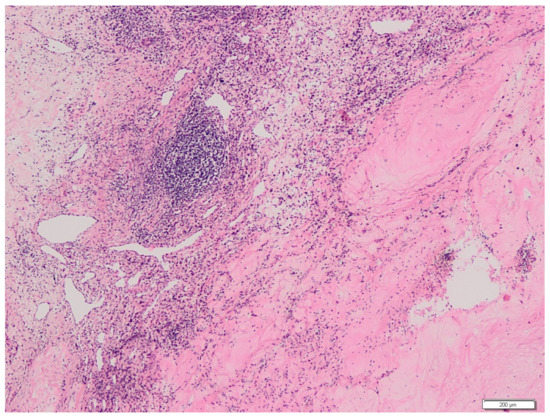

2. Case Presentation